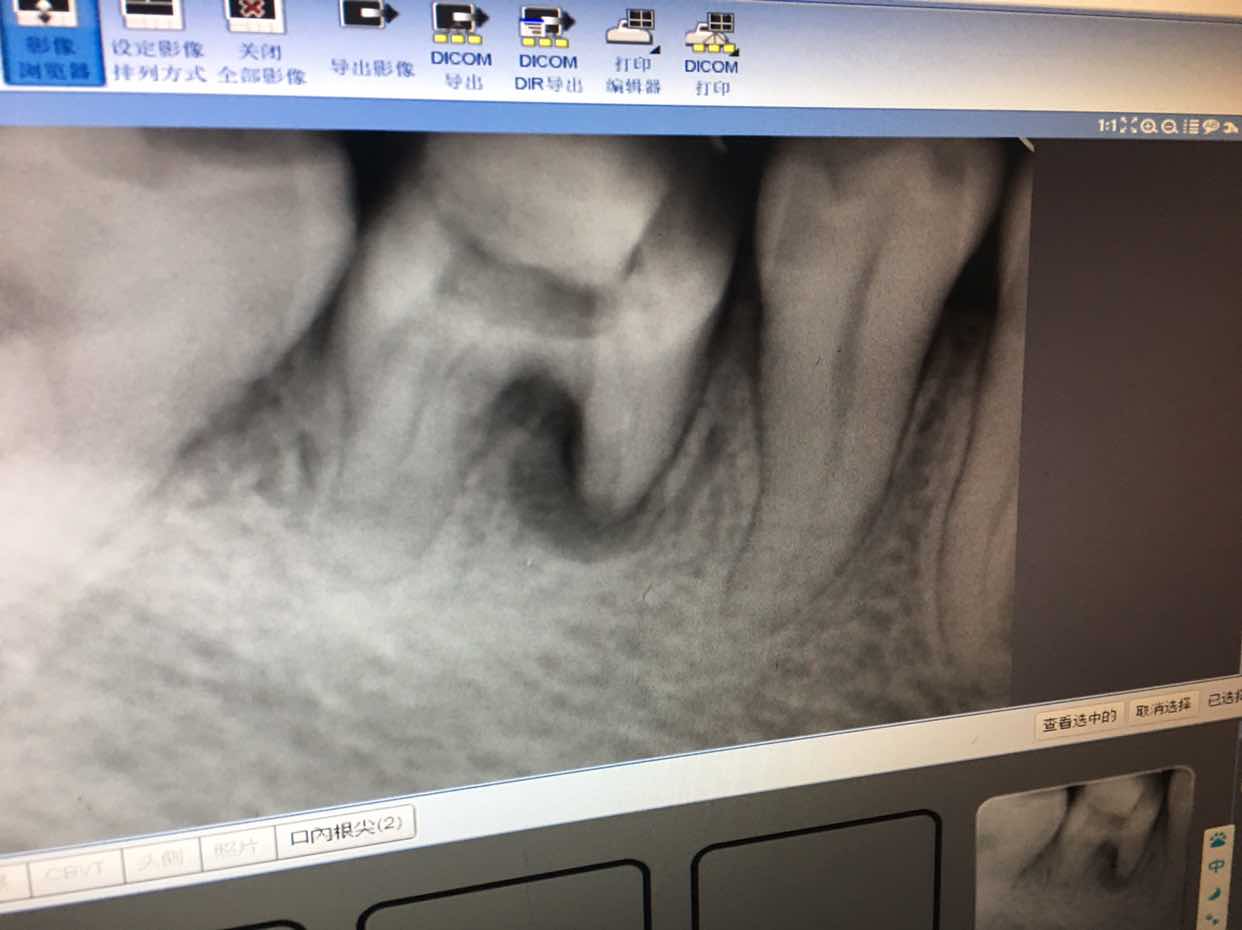

昨天终于去拔掉了右下46牙。拔之前跟大夫说明了身体状况,大夫坚持让查了个血常规才给拔。万幸的是虽然牙冠只剩了一点,但也一次性拔出来了,省去了抠牙根的麻烦。拔完后一直牙疼头晕,吃了甲硝锉和头孢,今天感觉好多了。

从三月份左上牙疼去拍片,结果发现右下46牙有炎症,本地医院一直治疗但根管一直疏通不了,建议去上级治疗,因为那边仪器先进些,可以显微根管治疗,没想到治了两次后,那边大夫也建议拔掉,没有保留的意义了。右上坏牙在上级医院做了根管治疗后,一直咬东西还有感觉,所以一直不能镶牙套,这个好悲催,本来根管治疗处理神经后大部分应该没有感觉了呀!来回折腾人力物力,这还仅仅是治疗,2500多的费用还没治彻底。牙齿有问题实在伤不起!